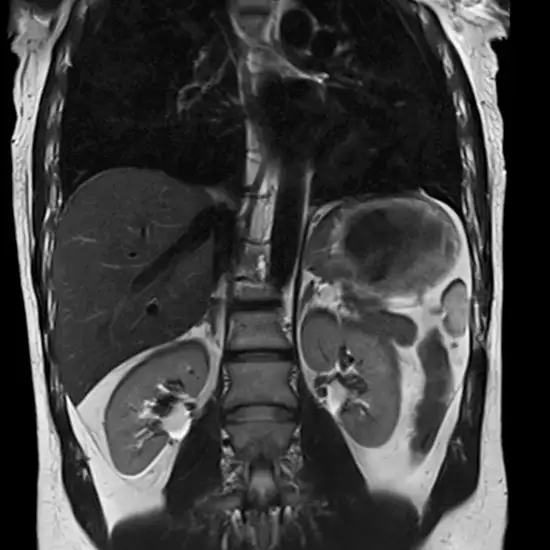

The screening of the upper abdomen is done to check the stomach pain and bloating.

Why is an MRI Screening Of the Upper Abdomen done?

It is needed to check kidney stones, tumours, diseases in the liver and other abnormalities in organs.

MRI Screening of the Upper Abdomen is an imaging diagnostic tool that is used to look for the conditions of the abdomen and surrounding areas. Patients should not avoid any symptoms related to abdomen and pancreatic injuries, abnormalities or disorders. Patients should go for screening to avoid any delay in diagnosis and treatment of the upper abdomen.